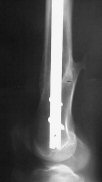

I presented a series of ~25 such cases at EuroTrauma'2004. Many cases were discussed here. I attach am example. Look also recent cases at http://www.hwbf.org/hwb/conf/alex58/scfx.htm,

Did you mark valgus malalignment in that case with LISS you posted Nov 9? Aplication of external distractor can help to avoid the pitfalls but some further development of the technology is necessary to shorten the learning curve.